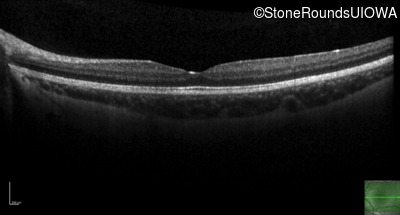

| Age at visit: 14 years |

| Age at visit: 14 years (Visit 2) |